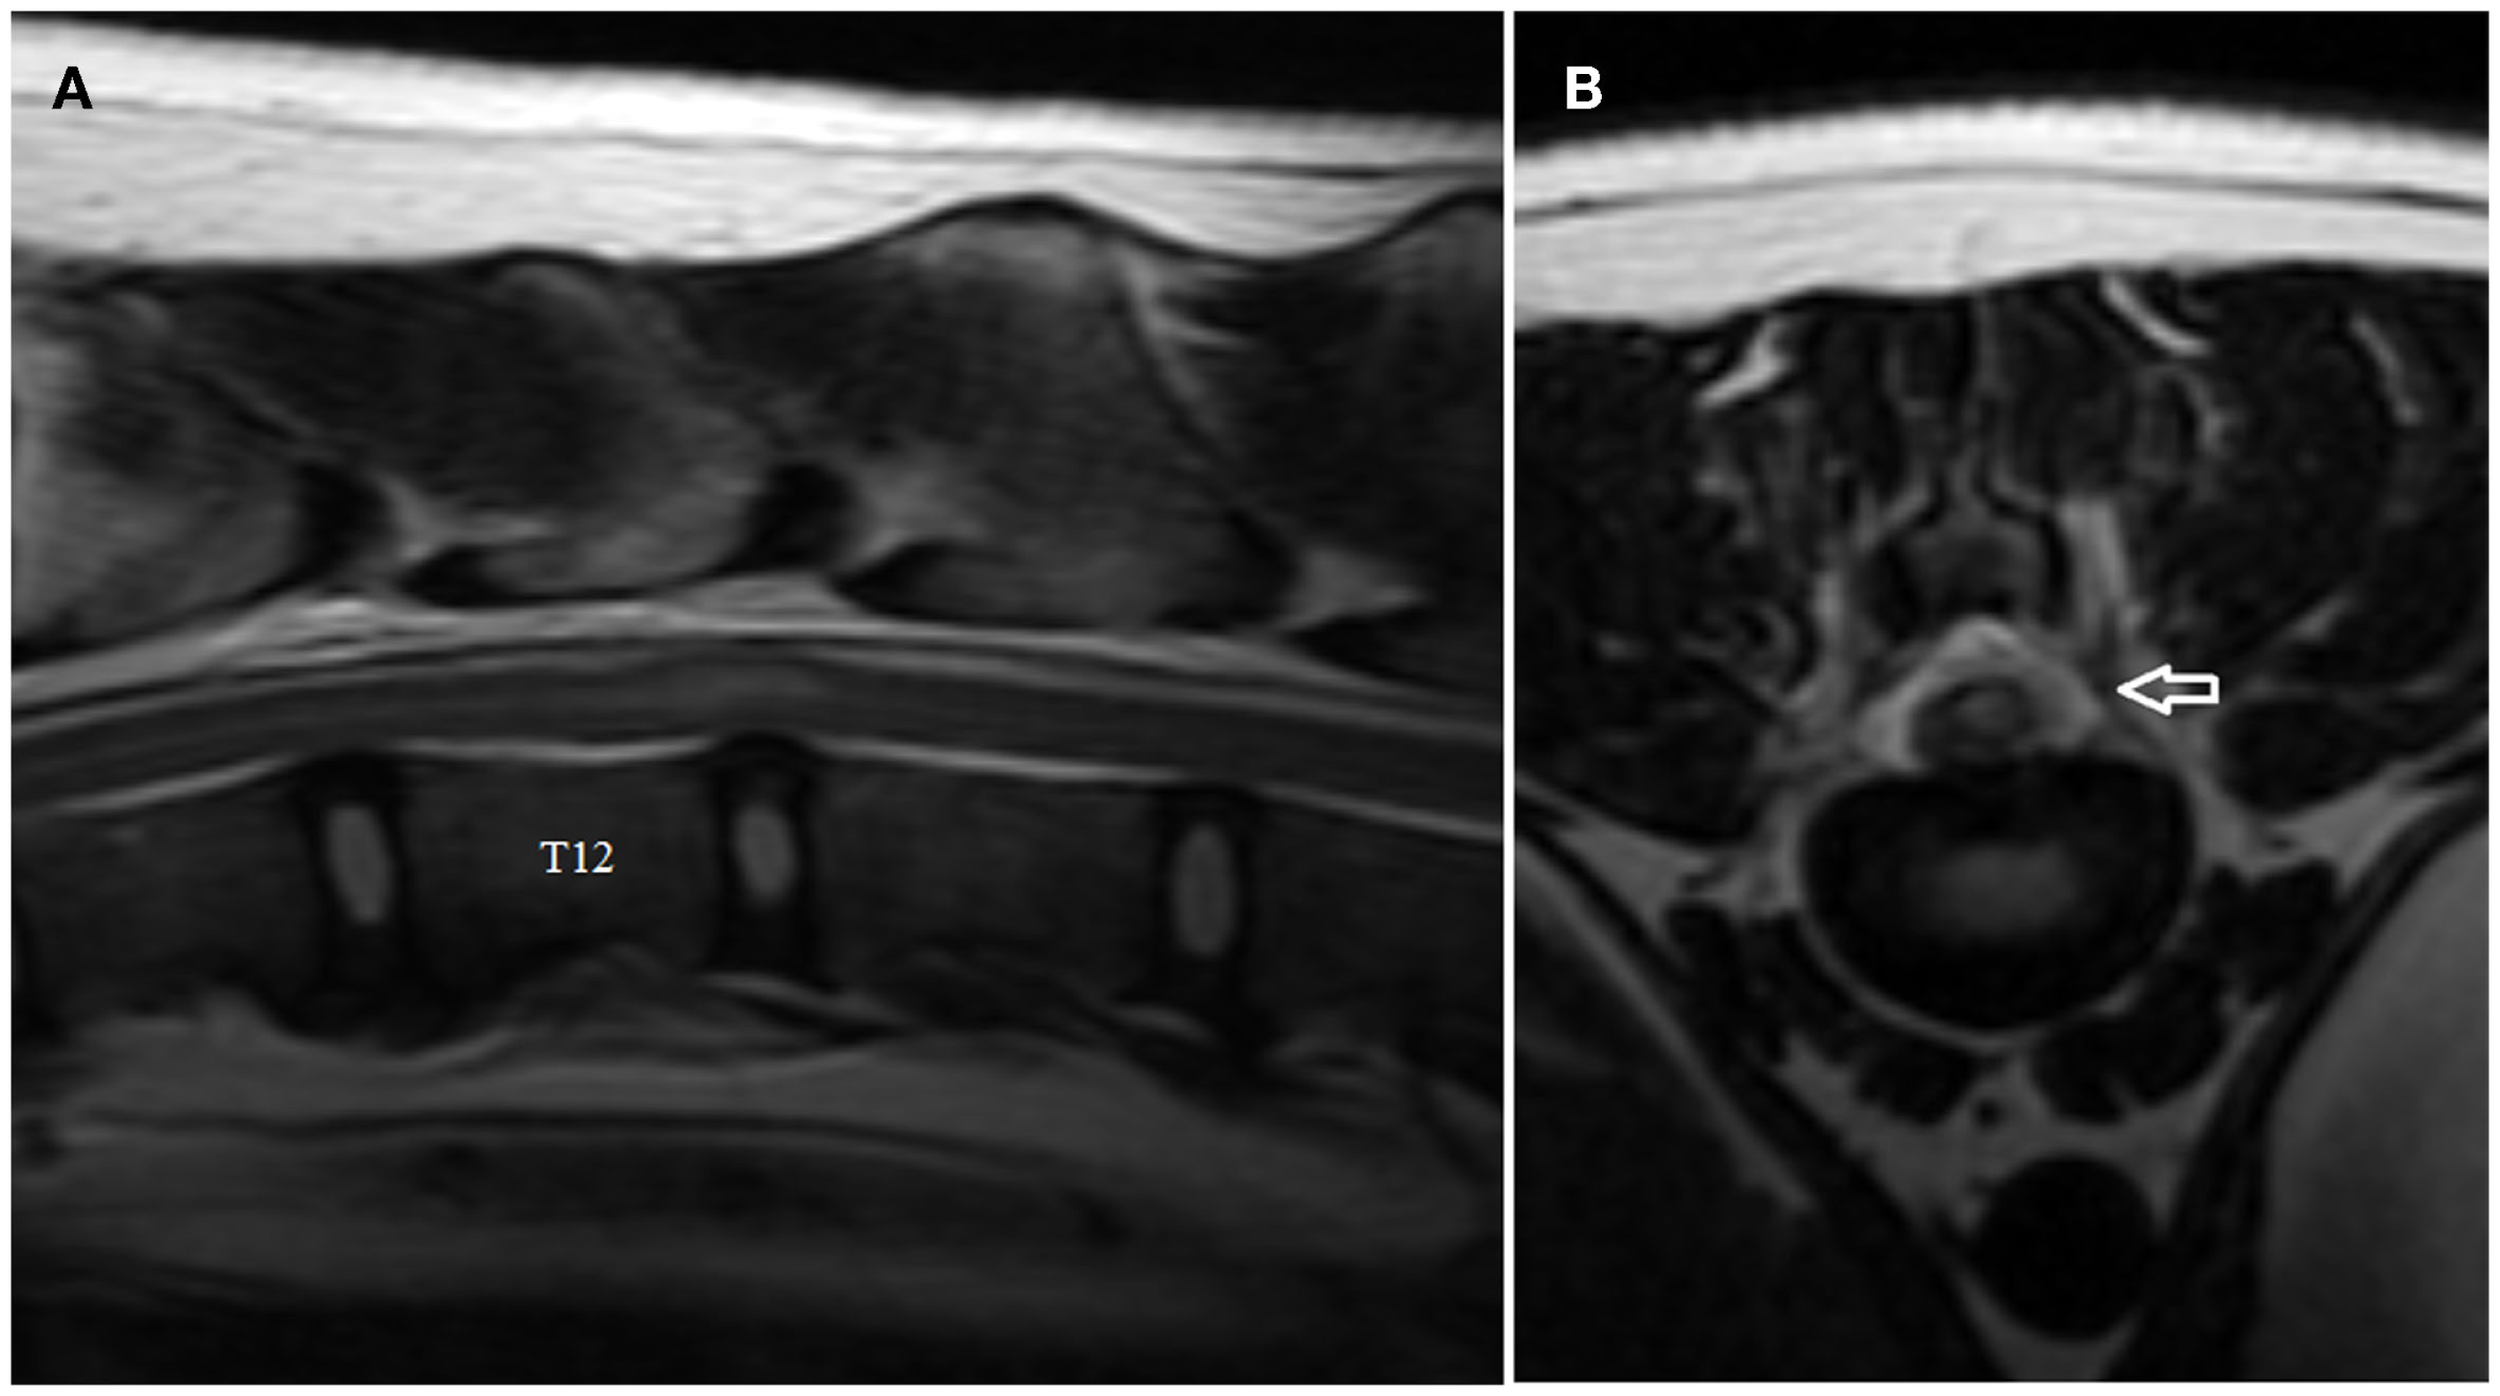

MRI Findings-FCEM

The MRI features suggestive of FCEM include a focal, relatively sharply demarcated intramedullary, and often lateralized lesion (edematous infarcted tissue), predominantly involving the gray matter that is hyperintense to normal gray matter on T2-weighted (Figures 1A,B) and FLAIR images and iso- or hypointense to normal gray matter on T1-weighted images. Post-contrast T1-weighted images may show mild and heterogeneous enhancement of the affected area, generally on the fifth to seventh day of disease (4, 6). The length of the intramedullary hyperintensity on T2-weighted images is generally longer than one vertebral length (6). MRI performed 24–72 h after onset of neurological signs may reveal no intraparenchymal signal intensity changes in dogs with FCEM (6). Repeated MRI 72 or more hours after onset of neurological dysfunction may allow identification of the spinal cord intramedullary changes (6). Diffusion-weighted MRI has been shown to increase the sensitivity for diagnosis of spinal cord infarction in the early stages of the disorder (47, 48). In research dogs with spinal cord ischemia induced by embolization of the spinal branches of intercostal arteries, diffusion-weighted imaging with a 1.5-T MRI showed slight hyperintensity within 1 h postembolization in all six examined dogs (49). Clinical application of diffusion-weighted imaging is technically challenging due to its sensitivity to susceptibility artifacts of bone and motion artifacts of CSF. Using a multi-shot technique improves signal to noise ratio and decreases sensitivity to off-resonance effects (49).

Figure 1. (A,B) Sagittal (A) and transverse (B) T2-weighted magnetic resonance images of the cervical spine of the English Bull Terrier shown in Video S1 in Supplementary Material. Note the intramedullary hyperintensity located above the C6 and the cranial half of C7 vertebral bodies. The spinal cord is swollen (Figure 2A). Note left-sided spinal cord intramedullary hyperintensity (arrow). There are no signal changes or extraneous material in the epidural space (Figure 2B).

The MRI features of ANNPE include a focal area of hyperintensity on T2-weighted images within the spinal cord overlying an intervertebral disk space, with absent or minimal spinal cord compression (Figure 2A) (17). The area of intramedullary hyperintensity on T2-weighted images is often lateralized and it is generally less than one vertebral length (Figures 2A,B) (17, 18). The region of spinal cord that corresponds to the focal hyperintensity on T2-weighted images is most commonly isointense on T1-weighted images and does not have evidence of enhancement on T1-weighted images obtained after administration of contrast agent. However, hypointensity on T1-weighted images and mild heterogenous enhancement on post-contrast T1-weighted images rarely occur (17, 18). There is decreased size and signal intensity of the affected nucleus pulposus on T2-weighted images and the intervertebral disk space is often narrowed (17, 18). Extraneous material or signal change may be evident in the epidural space dorsal to the affected intervertebral disk (Figure 2B).

FIGURE 2

Figure 2. Sagittal (A) and transverse (B) T2-weighted magnetic resonance images of the thoracolumbar spine of the boxer shown in Video S2 in Supplementary Material. Note the intramedullary hyperintensity located predominantly above the T12–T13 intervertebral disk space and the decreased size of nucleus pulposus (A). Note the signal change (arrow) in the left epidural space above the affected intervertebral disk and the left-sided spinal cord intramedullary hyperintensity (B).